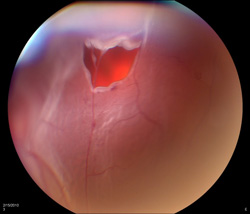

White laser photocoagulation spots surround a retinal tear